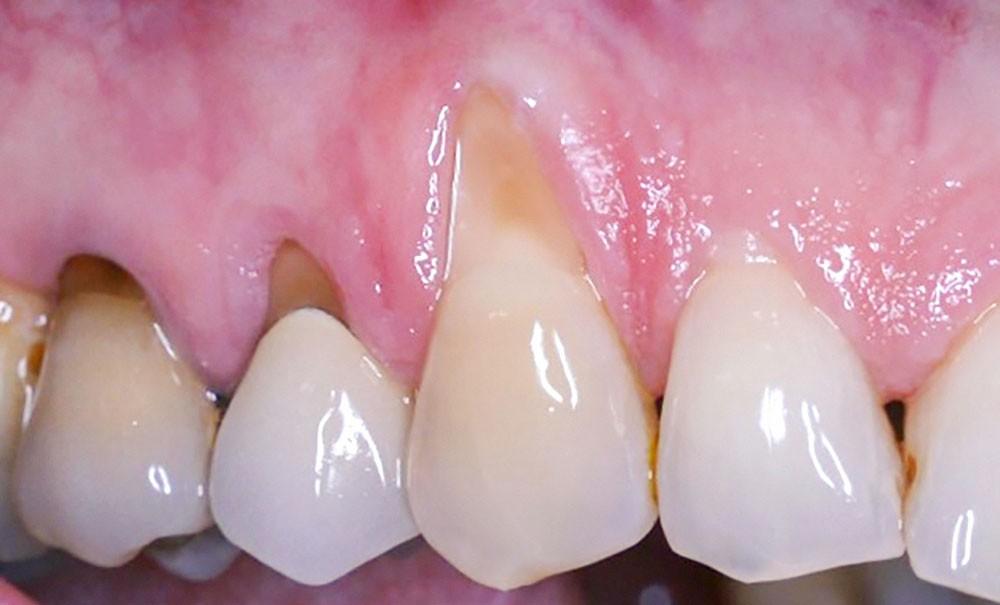

La greffe épithélio-conjonctive (GEC) [7, 8] consiste au remplacement du tissu parodontal existant par un greffon épithélio-conjonctif dont l’indication principale est l’augmentation en hauteur et en épaisseur du tissu kératinisé (fig. 2). Elle peut aussi être utilisée dans le recouvrement radiculaire (avec des résultats en termes de recouvrement inférieurs à ceux des techniques de greffe de conjonctif enfouie), l’aménagement des crêtes édentées, l’aménagement péri-implantaires [9, 10] (fig. 3), ou en association avec un traitement ortho-parodontal [11]. Le principal défaut de cette technique est son aspect inesthétique ; elle sera donc réservée à des zones non visibles comme les incisives mandibulaires ou les zones postérieures.